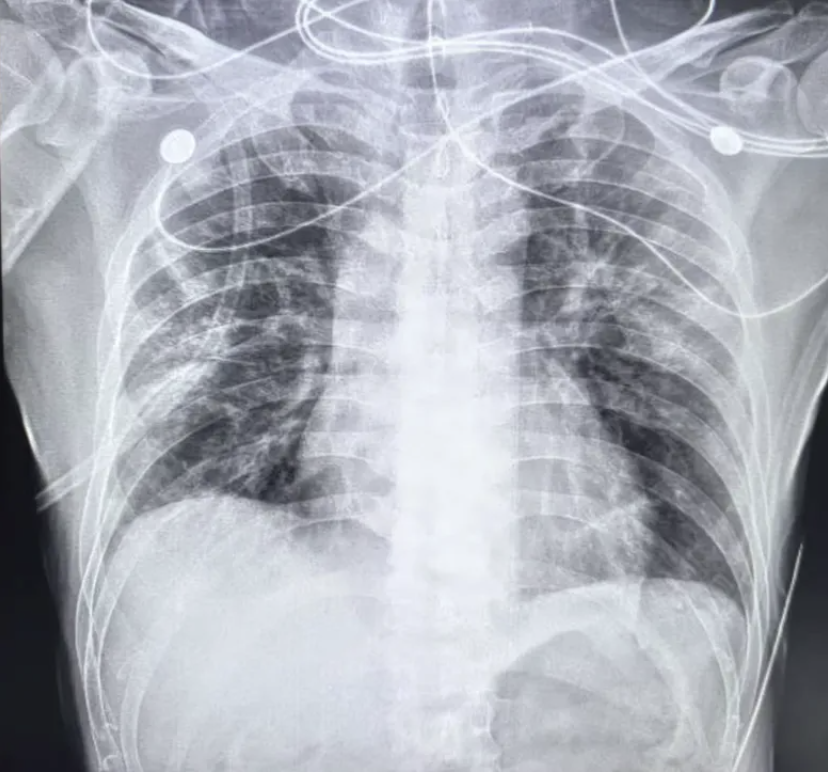

患者是一名四十多岁的中年男性,普通工人,既往无特殊粉尘或毒物接触史。此次因“发热、咳嗽、咳痰一周”来到门诊就诊。初步胸片检查显示(图1):右下肺散在渗出影,周围伴少许磨玻璃影。由于病变以单侧为主,门诊医生初步诊断为“社区获得性肺炎(CAP)”,并将患者收入呼吸科病房。

图1. 初步检查胸片

然而,复查时徐医生敏锐的发现:右下肺的磨玻璃影和渗出影非但没有减少,反而有局部增多趋势(图3)。但考虑这可能只是感染后的“延迟吸收”,加之患者自我感觉良好,便嘱咐其继续完成抗感染疗程。

图3. 复查胸片